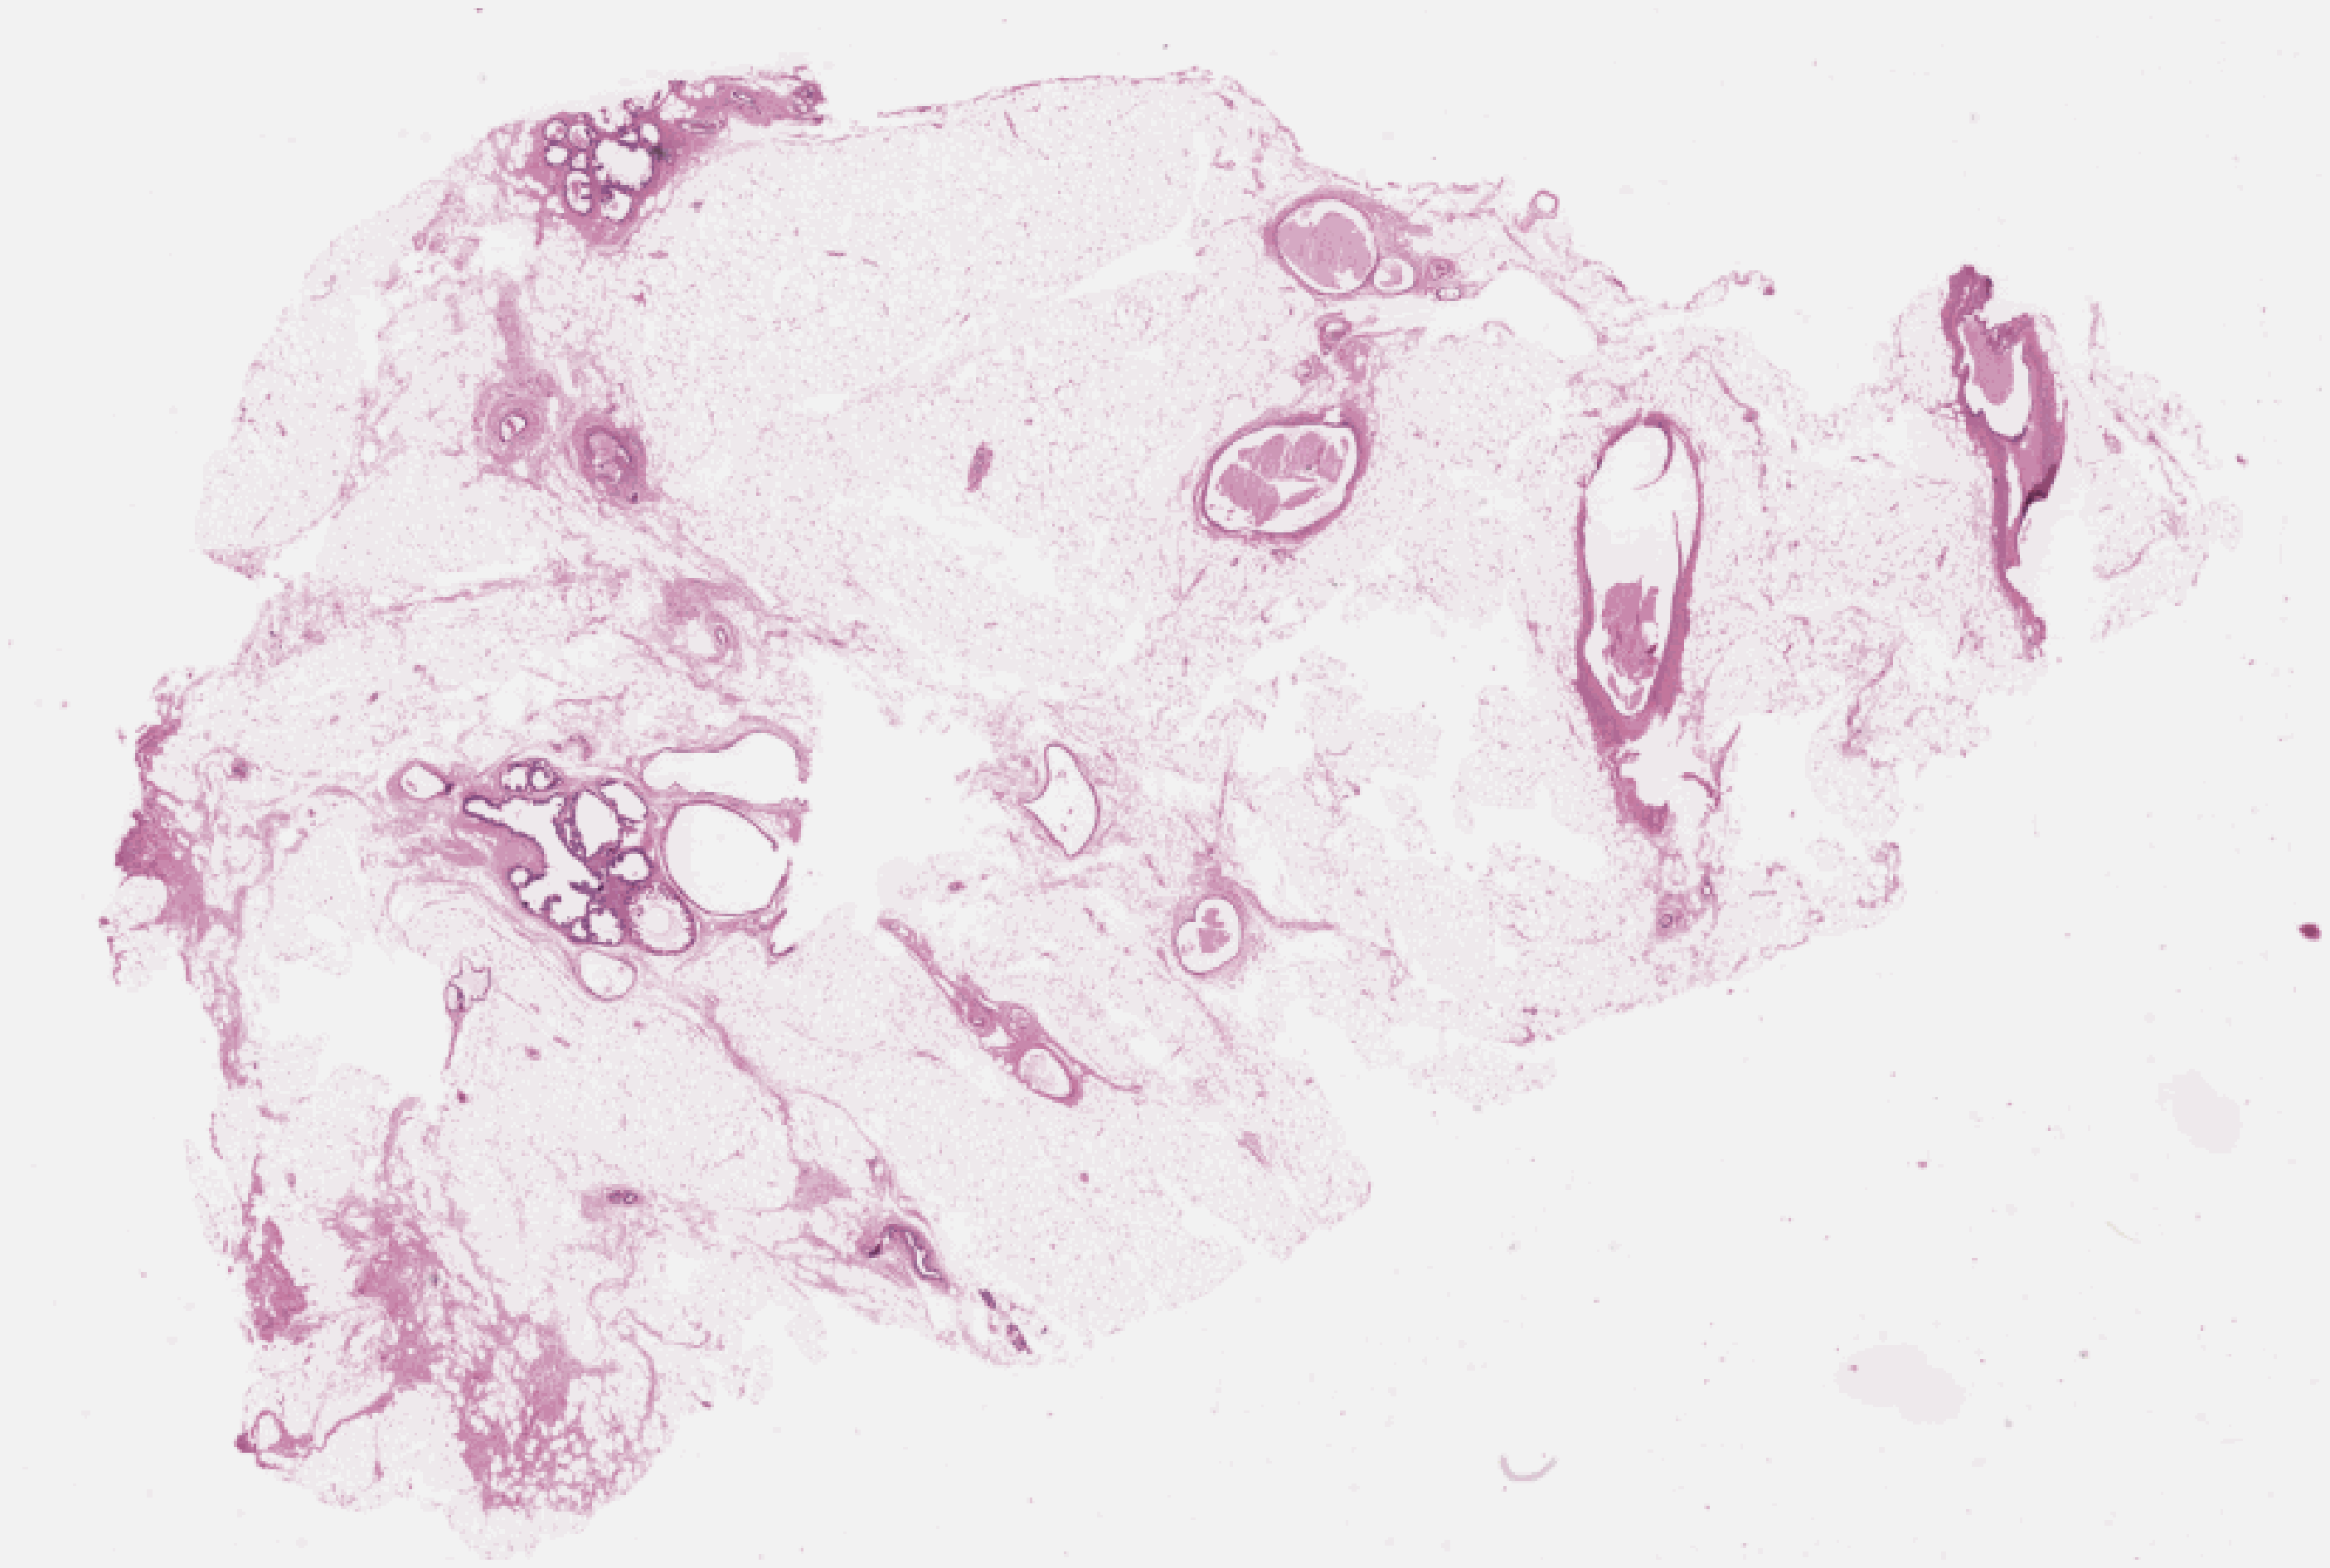

Whole-slide image with attention overlay highlighting suspicious tissue regions

TS-PSCAN · WSI 0142

H&E · attention overlay

Pan-cancer screening tool. Classifies H&E whole-slide images as cancer or normal across 11 tissue types. Outputs a calibrated risk score and attention heatmap. Available for research access upon request.